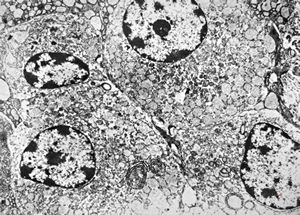

M,46y. | Entamoeba histolytica